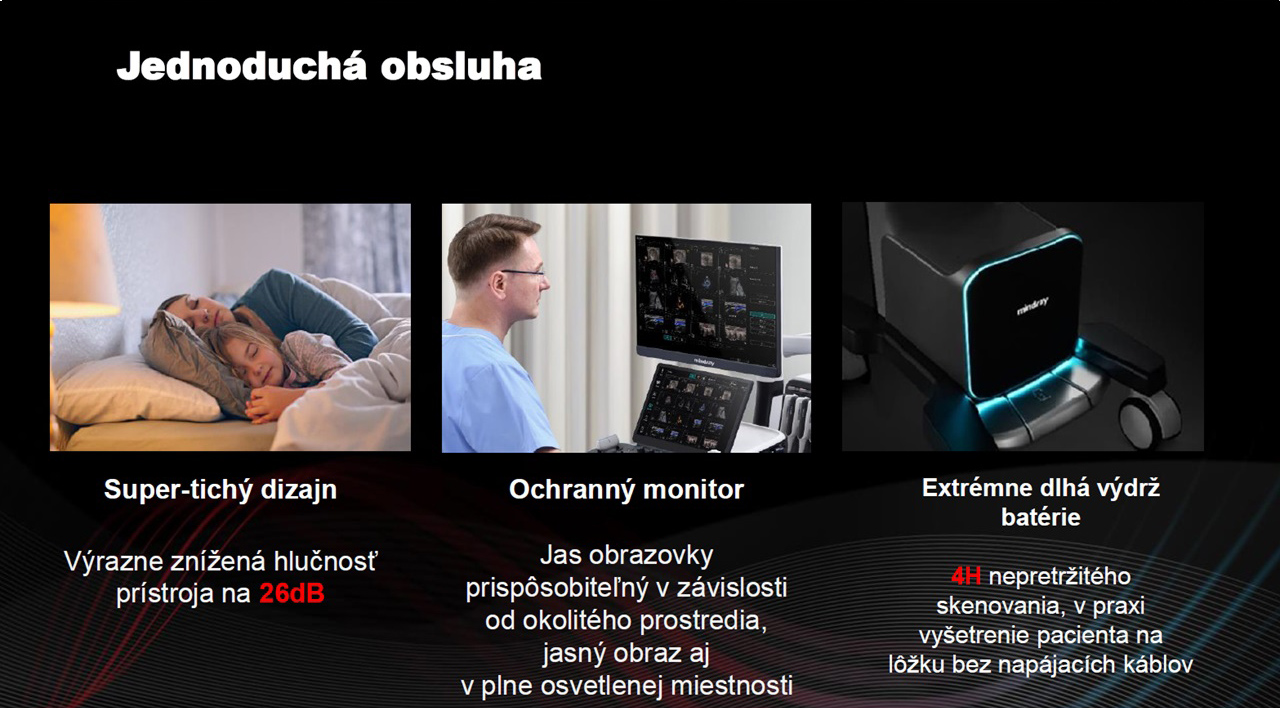

15,6 inch Full-HD dotykový ovládací panel s intuitívnou interakciou, intuitívny 3D / 4D náhľad, extrémne dlhá výdrž batérie 4 hodiny, super tichý dizajn 26dB, Hybrid hard disk (120GB SSD & 1TB HDD), DVD-R/W, 5+1 USB portov, 5 portov na pripojenie sond, zabudovaná WIFI